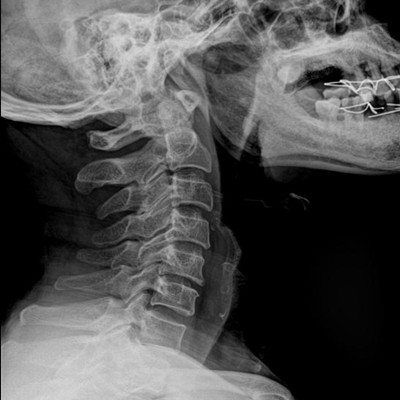

●探測器可以大范圍轉(zhuǎn)動,大尺寸有效探測面積,可滿足人體多部位攝影需求。